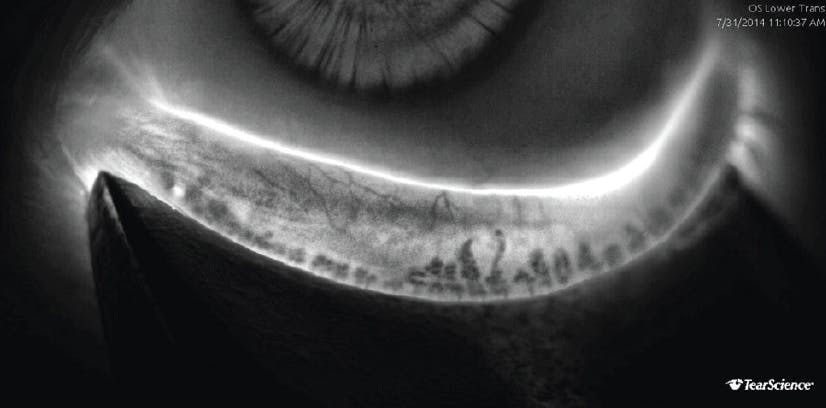

LipiScan noninvasively assesses meibomian gland structure; it uses dynamic illumination to minimize reflections and adaptive transillumination to provide equal lighting across the surface of the eyelids. Normal acini appear as discrete linear groups of light gray circular structures, whereas meibomian gland atrophy is seen as a darker gray absence of those structures. Serial images can be used to track the progress of therapy and improve patient compliance. Once meibomian glands atrophy, their function decreases, and their ability to regenerate is lost. Widespread destruction of glands seen on LipiScan images could therefore identify patients who may be less responsive to LipiFlow treatment (Figures 1–4).14

Figure 4. Adaptive transillumination with the LipiScan shows severe meibomian gland atrophy that may render treatment with the LipiFlow device less effective than it would be in a patient with less meibomian gland dropout.